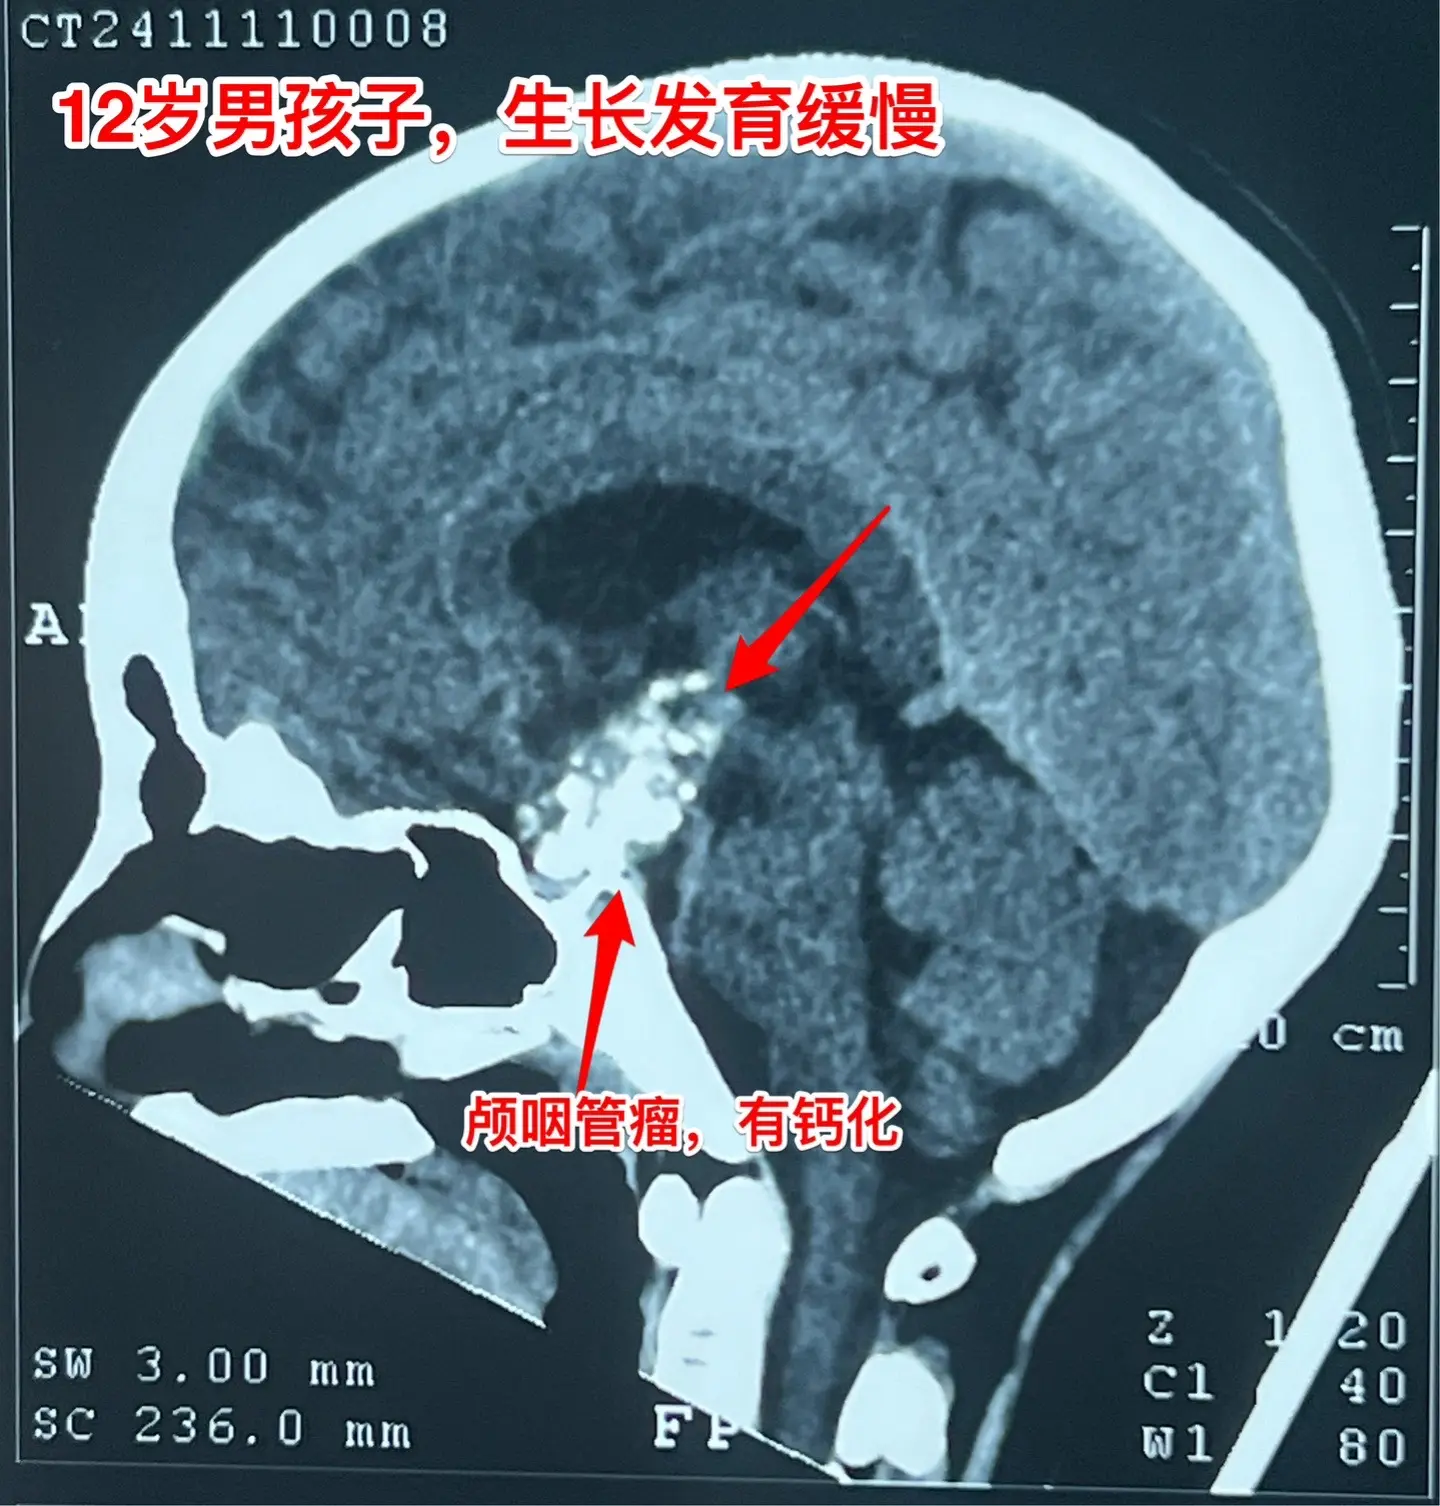

孩子生长发育缓慢,家长要重视。这个12岁的男孩子,在深圳生活,平时爱运动,除了生长发育缓慢之外似乎很“健康”。视力无下降,无头痛症状。 父母观察到孩子的生长发育问题,到医院去检查,发现脑部长了肿瘤,是典型的颅咽管瘤,有钙化。 这个颅咽管瘤是沿着垂体柄内部上下方向生长的,向上长进了第三脑室。这样的颅咽管瘤完全切除的难度比较大,垂体柄也难以保留。 2024.11.15顺利切除肿瘤。手术后患者患者很快就清醒了,从ICU转回来普通病房。希望肿瘤不复发。